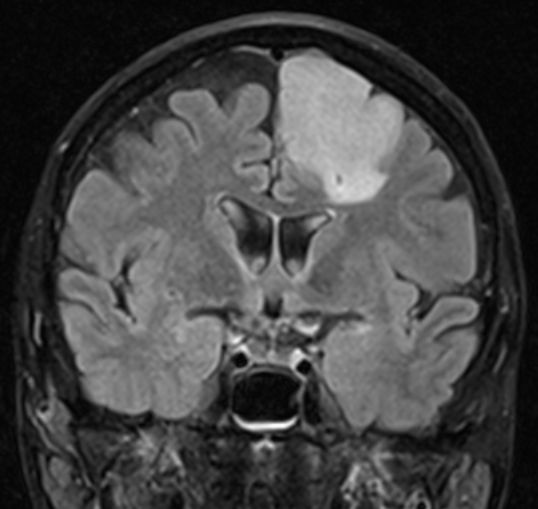

61-jährige Frau mit einem diffusen Astrozytom Grad II | ||

Primärbefund |

MRT T2 Tse |

MRT T2 Tirm![]() |